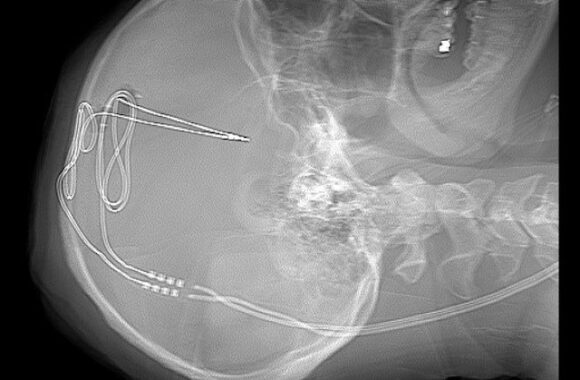

Smegenų implantai išbandomi gydant priklausomybę nuo narkotikų